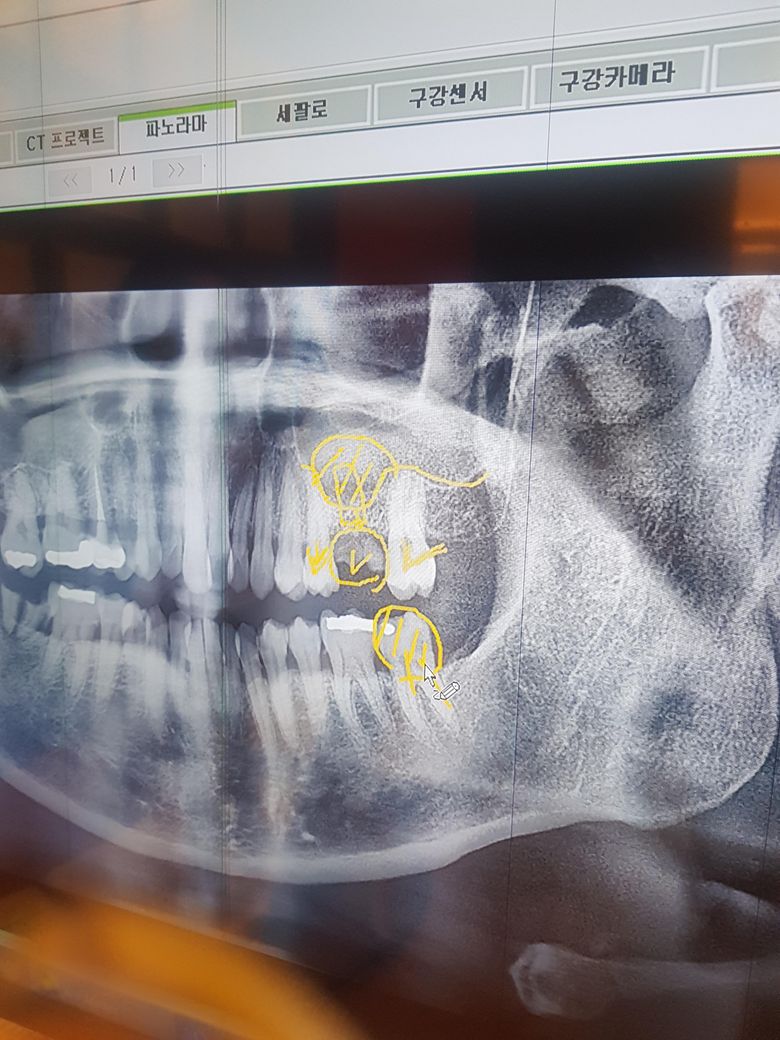

위어금니옆에 파절된지 몇년지났는데 그쪽으로 씹어도 안아프길래 병윈안가다가아래어금니 48번아말감이 일부깨젰는데 아파서 병원갔는데 실장님이 윗쪽은 무조건 임플란트하고 뻐이식비용이 50든다고 하는데요. 아직48세인데 뼈이식을 꼭해야하나요? 뼈가부족한지 안한지 어떻게알까요?전브릿지하고싶은데 실장님은 임플란트 강추하세요 ㅠ 아직임플란트는 안하고싶은데 사진첨부합니다. 조언부탁드레오

• 2번 째 사진

파노라마 상으로는 뼈가 어느정도 임플란트 심기에는 충분해 보이지만 정확한건 CT를 찍어보셔야될것같습니다.

1. 일단 설명들으신 부분은 20번, 30번대 치아입니다. 파노라마 사진상에서는 좌우대칭입니다. 사진상 오른쪽이 실제로는 왼쪽 위, 아래입니다.

2. 20번대 (실제 왼쪽 위) 어금니 부위는 브릿지도 가능하지만 임플란트가 더 최신 술기이긴 합니다. 다만, 상악동이라는 위턱뼈 빈 공간 구조가 잇몸뼈 부위쪽으로 침범해서 뼈이식은 불가피할 것 같습니다. 임플란트와 브릿지는 상황에 따라 각기 장,단점이 있습니다. 수술이 싫고 브릿지를 강력히 원한다면 다른 치과를 알아보는 것도 좋습니다.

3. 37번 아말감 깨진 것도 처치를 너무 늦지 않게 받는 것이 좋습니다.